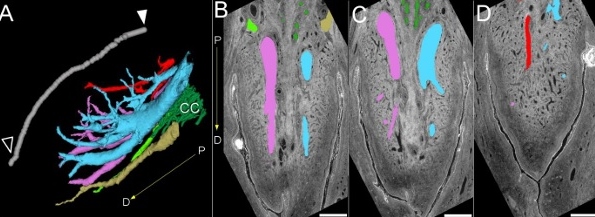

Granskarar hava gjørt tvær framkomnar 3D-skanningar, sum geva óvanligt innlit í nervarnar í viðkvæma organinum.